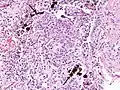

Micrograph of asbestosis showing the characteristic ferruginous bodies and marked interstitial fibrosis (or scarring). H&E stain.

Asbestosis is the scarring of lung tissue (beginning around terminal bronchioles and alveolar ducts and extending into the alveolar walls) resulting from the inhalation of asbestos fibers. There are two types of fibers: amphibole (thin and straight) and serpentine (curly). All forms of asbestos fibers are responsible for human disease as they are able to penetrate deeply into the lungs. When such fibers reach the alveoli (air sacs) in the lung, where oxygen is transferred into the blood, the foreign bodies (asbestos fibers) cause the activation of the lungs' local immune system and provoke an inflammatory reaction dominated by lung macrophages that respond to chemotactic factors activated by the fibers.[20] This inflammatory reaction can be described as chronic rather than acute, with a slow ongoing progression of the immune system attempting to eliminate the foreign fibers. Macrophages phagocytose (ingest) the fibers and stimulate fibroblasts to deposit connective tissue.

Due to the asbestos fibers' natural resistance to digestion, some macrophages are killed and others release inflammatory chemical signals, attracting further lung macrophages and fibrolastic cells that synthesize fibrous scar tissue, which eventually becomes diffuse and can progress in heavily exposed individuals. This tissue can be seen microscopically soon after exposure in animal models. Some asbestos fibers become layered by an iron-containing proteinaceous material (ferruginous body) in cases of heavy exposure where about 10% of the fibers become coated. Most inhaled asbestos fibers remain uncoated. About 20% of the inhaled fibers are transported by cytoskeletal components of the alveolar epithelium to the interstitial compartment of the lung where they interact with macrophages and mesenchymal cells. The cytokines, transforming growth factor beta and tumor necrosis factor alpha, appear to play major roles in the development of scarring inasmuch as the process can be blocked in animal models by preventing the expression of the growth factors.[21][22] The result is fibrosis in the interstitial space, thus asbestosis.